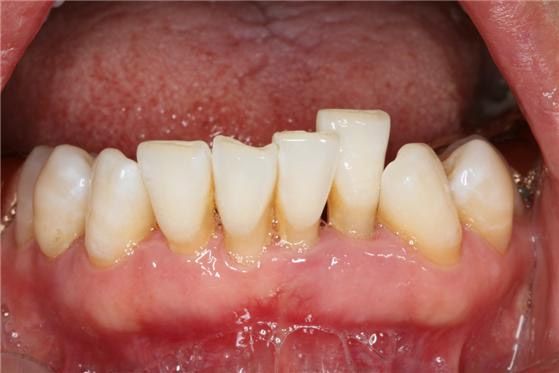

잇몸 조직 소실되며 치아 뿌리가 노출되는 현상인 ‘치은퇴축’은 중장년층이나 노년층에서 주로 나타나지만, 치아 외상 등에 의해 젊은 연령에서도 자주 발생한다.

치은퇴축은 중장년층이나 노년층에서는 잇몸병(치주질환)으로 인해, 젊은 연령층에서는 치아의 외상 등에 의해 치주조직이 얇은 부위에서 발생한다. 문제는 한 번 내려앉은 잇몸은 심미적인 문제 외에도 통증 등을 동반할 수 있어 그 예방과 치료에 각별한 주의가 필요하다는 것이다.

잇몸이 치아 뿌리 방향으로 내려가 치근(치아 뿌리)이 노출되면, 차고 뜨거운 것에 민감해질 수 있다. 또, 치아 사이 공간이 넓어지면 음식물이 빈번하게 끼기도 하고, 노출된 치근면이나 인접 면에 충치가 발생할 수 있다. 치아 사이가 벌어져 평소보다 음식물이 많이 끼거나 앞니의 뿌리가 이전보다 많이 보이고 치아가 길어진 것 같이 느껴진다면 잇몸 점검을 받아볼 필요가 있다.

치은퇴축의 치료법으로는 퇴축된 부위 아래 및 측면부 잇몸을 이동시키는 잇몸 성형술과 잇몸 이식술 등이 있다. 잇몸 이식술은 구개(입천장) 측에서 충분한 양의 결합조직 이식 편을 채취해 퇴축 부위에 덮는 방식으로 진행한다. 치료를 통해 노출된 치아 뿌리를 덮고 잇몸의 높이와 부피를 회복할 수 있다. 이에 앞서, 치주질환으로 인해 전반적인 치조골 소실과 치은퇴축 양상이 관찰되는 경우에는 철저한 치주치료로 더 이상의 퇴축을 방지하는 것이 필수적이다.